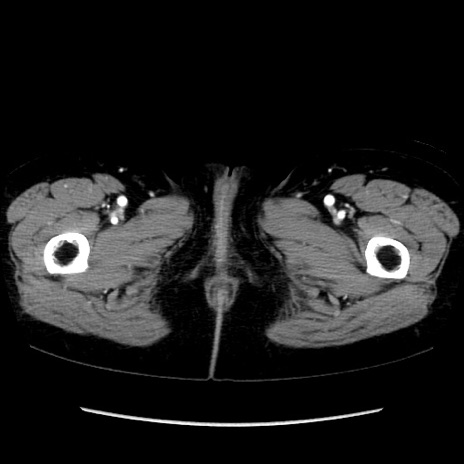

症例32(横断像)

【症例】40歳代 女性

【主訴】上腹部痛、嘔気・嘔吐

【現病歴】約9時間前頃から急に上腹部痛、嘔気、嘔吐が出現。改善しないため救急要請。

【既往歴】子宮頚癌(広汎子宮全摘術、放射線療法)、腸閉塞

【身体所見】腹部:平坦、軟、腸雑音亢進、上腹部を中心に腹部全体に圧痛あり。

【データ】WBC 8400、CRP 0.03